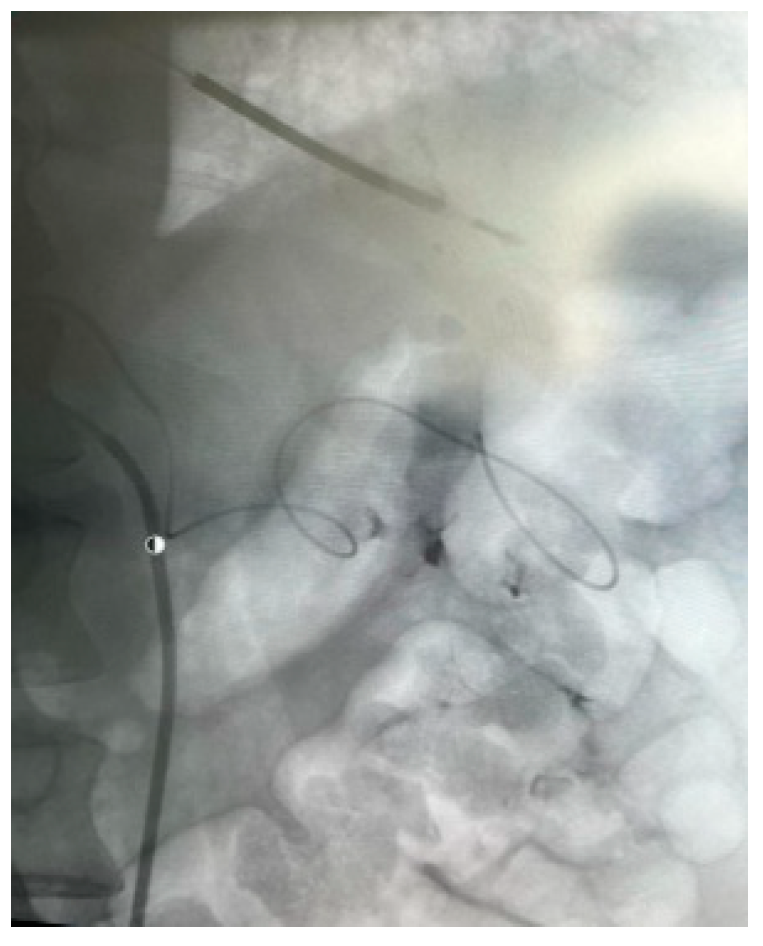

Appendix A.2. Clinical Case 2: Treatment of Endoleak Type II Inferior Mesenteric Artery